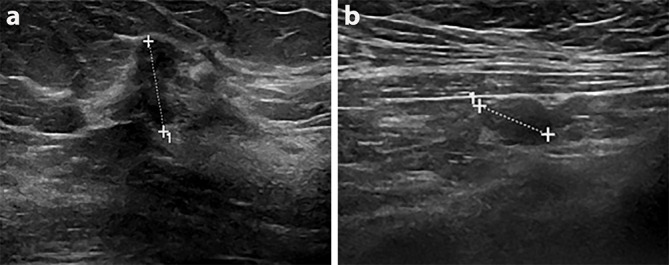

超极化 13C 磁共振成像(HP-MRI)是一种新型成像技术,可对体内代谢途径进行实时分析1 。随着分子生物学知识的发展,人们越来越清楚地认识到癌细胞代谢与疾病结果的关系,其中乳酸引起了特别关注。2 近期对乳腺癌筛查项目的审查引起了人们的关注,并提高了公众对过度治疗的认识。科学界需要将重点从单纯提高癌症检测率转移到寻求新的方法来区分侵袭性乳腺癌和仍将保持不扩散的乳腺癌。HP-MRI 为识别侵袭性肿瘤表型和帮助监测/预测治疗反应提供了机会。在此,我们报告了首例使用 HP-MRI 和包括乳腺 MRI 在内的相关传统成像技术进行成像的乳腺癌病例。

Hyperpolarised 13C MRI (HP-MRI) is a novel imaging technique that allows real-time analysis of metabolic pathways in vivo.1 The technology to conduct HP-MRI in humans has recently become available and is starting to be clinically applied. As knowledge of molecular biology advances, it is increasingly apparent that cancer cell metabolism is related to disease outcomes, with lactate attracting specific attention. 2 Recent reviews of breast cancer screening programs have raised concerns and increased public awareness of over treatment. The scientific community needs to shift focus from improving cancer detection alone to pursuing novel methods of distinguishing aggressive breast cancers from those which will remain indolent. HP-MRI offers the opportunity to identify aggressive tumour phenotypes and help monitor/predict therapeutic response. Here we report one of the first cases of breast cancer imaged using HP-MRI alongside correlative conventional imaging, including breast MRI.